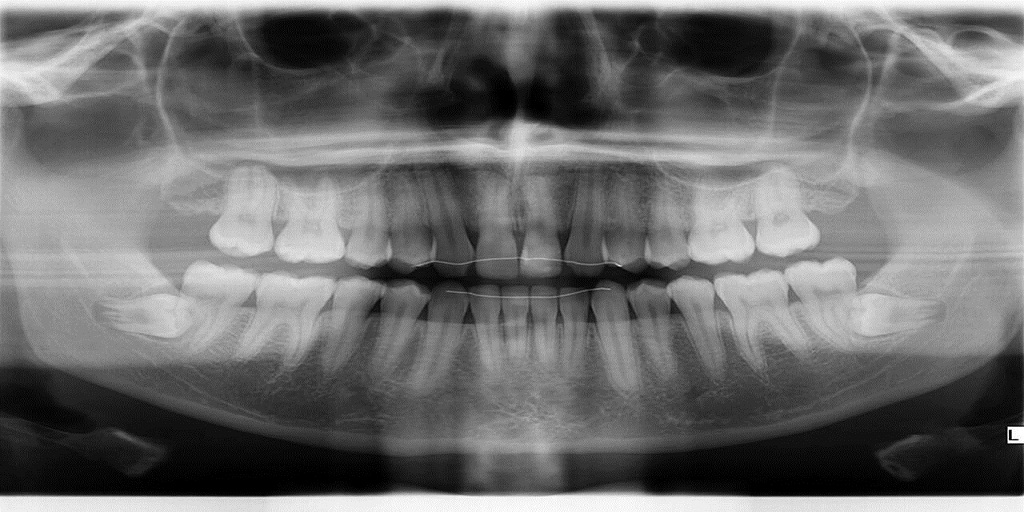

The Instrumentarium OP300 digital dental X-ray machine provides high-quality panoramic X-rays that are ideal for the day-to-day needs of dental practices. The OP300 also provides more advanced panoramic imaging programs, including ortho zone, orthogonal, wide arch and extraoral bitewing views.

The Instrumentarium OP300 3D panoramic + ceph + cone beam system is a 3-in-1 dental CBCT machine that delivers three imaging capabilities: panoramic, cephalometric, and small field of view cone beam scans, which are perfect for surgical guides and implant placement.

The Instrumentarium OP300 CBCT modality offers a FOV size of 6 x 4 cm specifically for localized exams, such as endodontics, and also a 6 x 8 cm FOV to capture an entire arch for surgical guides and implant placement.